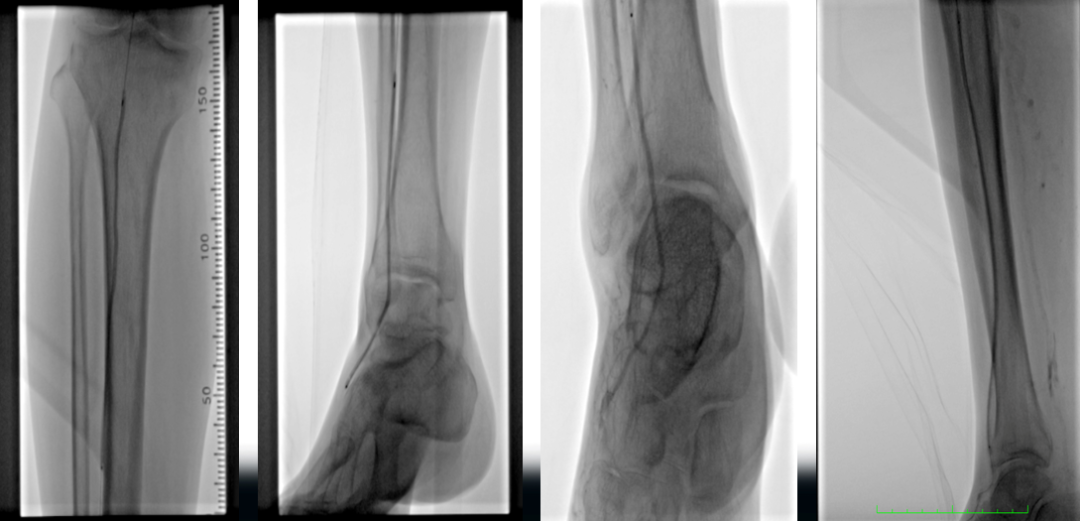

辅助检查:ABI(左0.72,右0.56),下肢动脉彩超显示双下肢动脉硬化伴多发斑块,右侧股浅动脉上段闭塞,双侧胫前动脉中下段接近闭塞。CTA提示:腹主动脉粥样硬化,右侧股动脉、双侧胫前动脉中重度狭窄、闭塞,左侧股动脉、双侧腓动脉、胫后动脉轻度狭窄,左侧髂内动脉局限性闭塞。

术前CTA

术前造影